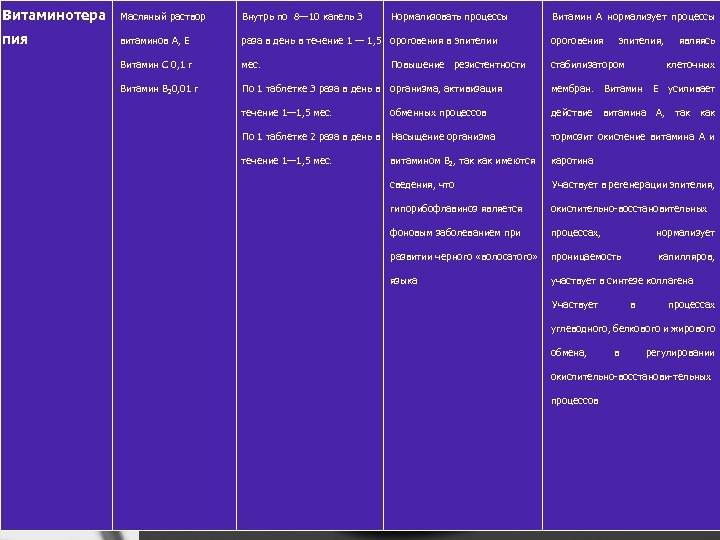

Витаминотера Масляный раствор Внутрь по 8— 10 капель 3 пия витаминов А, Е раза в день в течение 1 — 1, 5 ороговения в эпителии ороговения Витамин С 0, 1 г мес. стабилизатором Витамин В 20, 01 г По 1 таблетке 3 раза в день в организма, активизация мембран. Витамин Е усиливает течение 1— 1, 5 мес. действие витамина А, так как Нормализовать процессы Повышение резистентности обменных процессов Витамин А нормализует процессы эпителия, являясь клеточных По 1 таблетке 2 раза в день в Насыщение организма тормозит окисление витамина А и течение 1— 1, 5 мес. витамином В 2, так как имеются каротина сведения, что Участвует в регенерации эпителия, гипорибофлавиноз является окислительно восстановительных фоновым заболеванием при процессах, нормализует развитии черного «волосатого» проницаемость языка капилляров, участвует в синтезе коллагена Участвует в процессах углеводного, белкового и жирового обмена, в регулировании окислительно восстанови тельных процессов